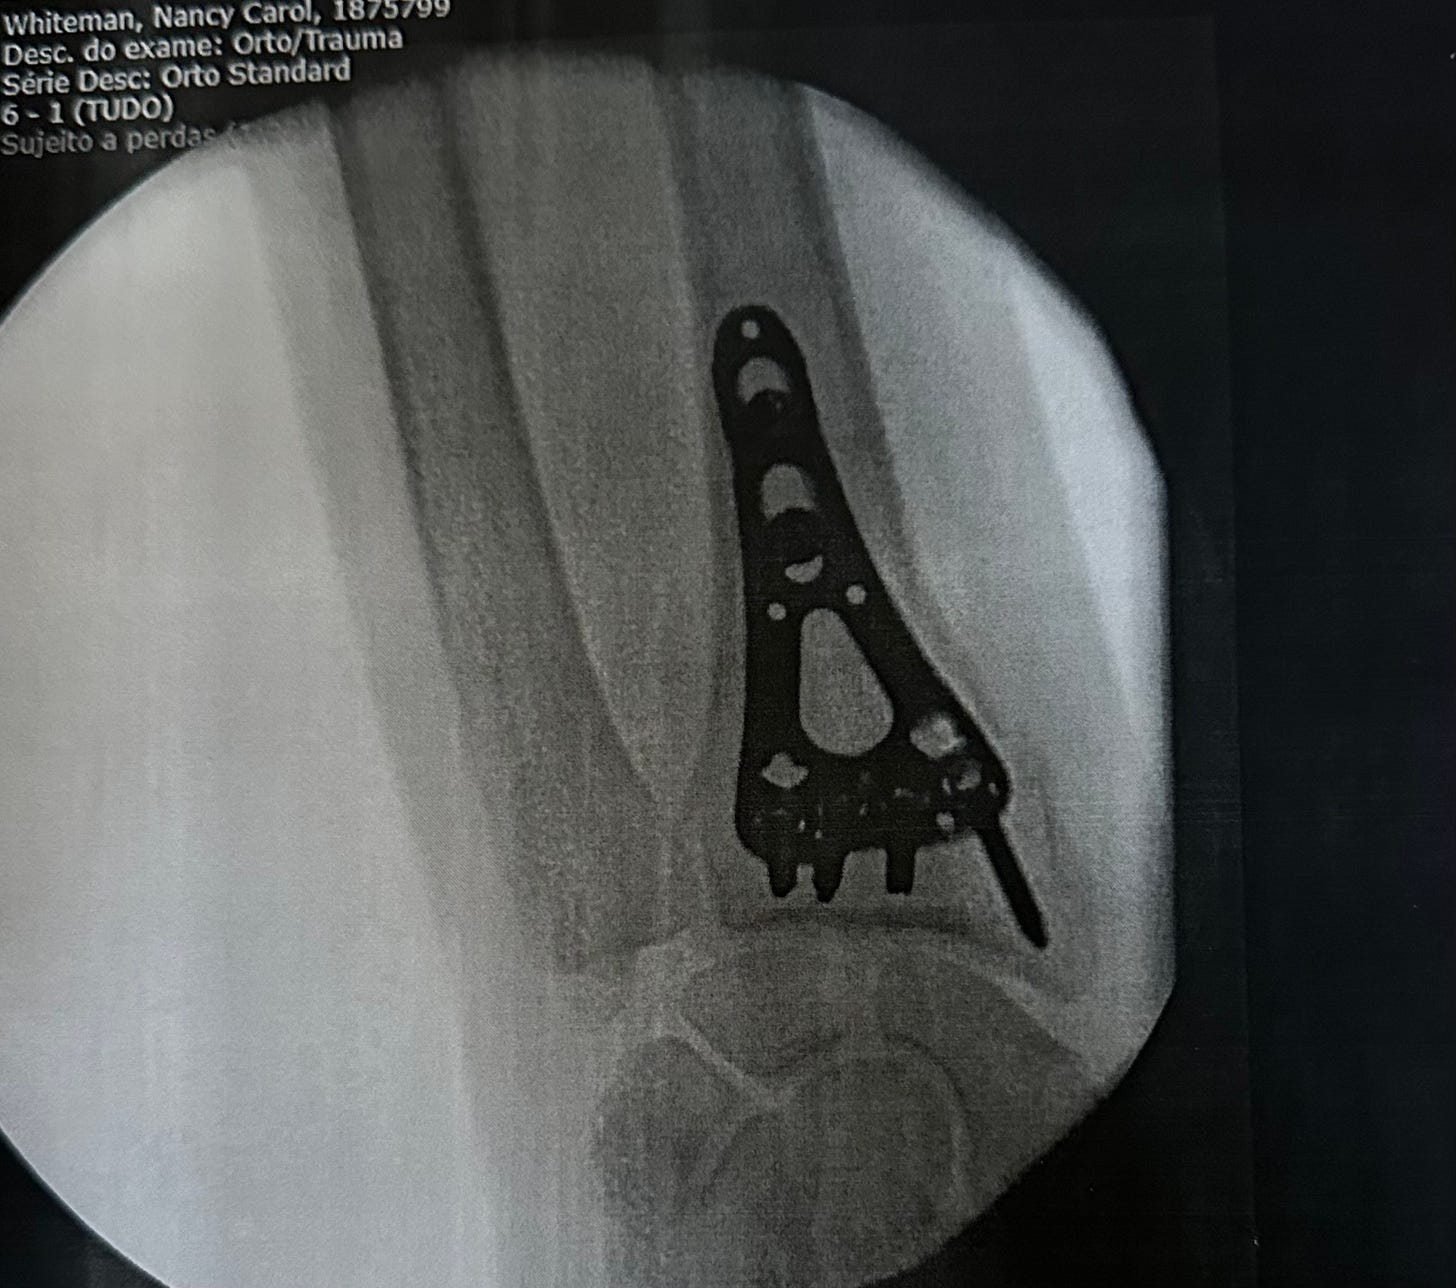

At around 18:30, they wheeled my bed to the OR. A few more questions from the anesthesiologist and off to la-la-land. Within the hour, I was waking up in post op in the bed I had arrived in. I was taken back to my room and told they would give me tea and cookies at 07:00 and disconnect the IV so I could get up. And that is exactly what happened.

Dr Maria appeared at 9:00 to check on me. She explained that her associate, who had assisted with the surgery, would see me the next day at the VRSA clinic. She had completed her discharge papers, and as soon as the nurse removed the IV from my arm, I was free to go. She also provided me with the photo above. I called Denise, and within 2 hours, I was home again.